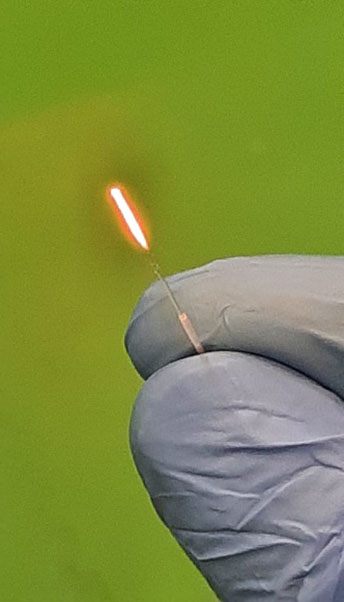

Customized single use Ball tip Fiber for Percutaneous Laser Disk Decompression (PLDD)

Properties |

Fiber type |

400um bare fiber |

Fiber length |

3m |

Connector type |

SMA905 or HP-SMA905 |

Distal tip Sterilization |

Ball tip EtO-sterilized |